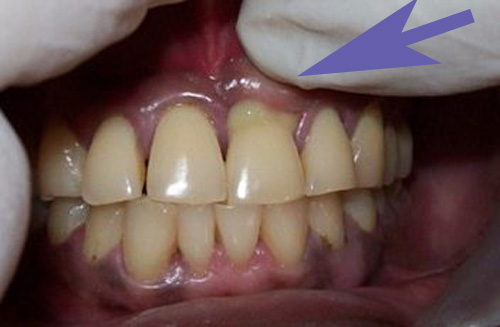

Помимо вышеперечисленных признаков, выявляются увеличенные лимфатические узлы, болезненные при пальпации. Конфигурация лица меняется, становится асимметричной. Гнойное изменение десны можно увидеть на фото.